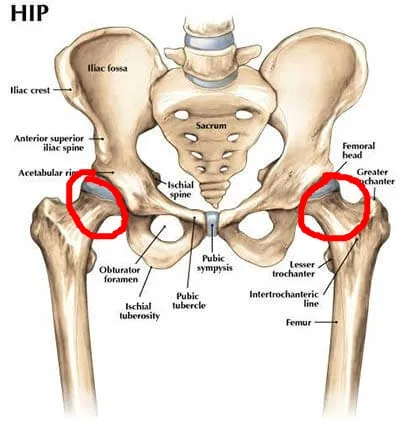

고관절 질환 1. 고관절 충돌 증후군

고관절을 이루는 비구(골반의 컵 모양 소켓)와 대퇴골두(허벅지 뼈의 공 모양 끝부분), 그리고 경부(대퇴골두와 허벅지 뼈를 연결하는 부위)의 구조가 서로 충돌하면서 통증을 일으키는 질환입니다. 관절 사이의 충돌이 오랜 기간 반복되면 충돌 부위의 관절 연골이 손상되고, 비구(소켓에 붙어 있는 연골)나 대퇴골에 붙어 있는 섬유 연골 조직이 찢어져 통증을 유발할 수 있습니다.